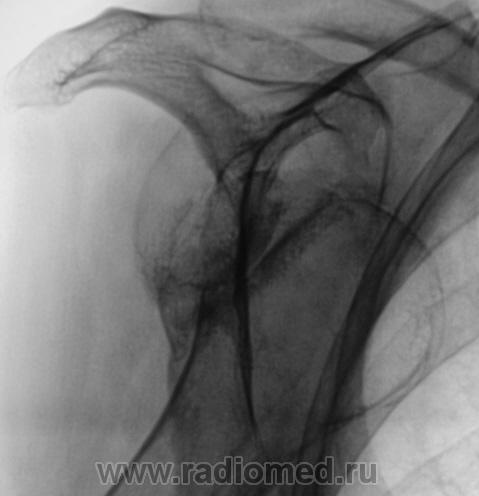

Пол пациента: Мужской пол Тип патологии: Другое Область исследования: Скелетно-мышечная система Методы исследования: Rg Пацент направлен на рентгенографию грудной клетки. Было обращено внимание на "застарелый" вывих головки плечевой кости с образованием "нового, патологического" сустава, с хорошо сформированными "суставными поверхностями". Ваше мнение коллеги? Втр, 06/10/2009 - 07:41 #1 OPEXOB Не на сайте Был на сайте: 9 лет 11 месяцев назад Зарегистрирован: 26.07.2008 - 10:02 Публикации: 280 Это "ужасы" нашего здравоохранения. Страх пациента обращаться в медицинские учреждения и, как не печально "тупость" сожителей пациента.